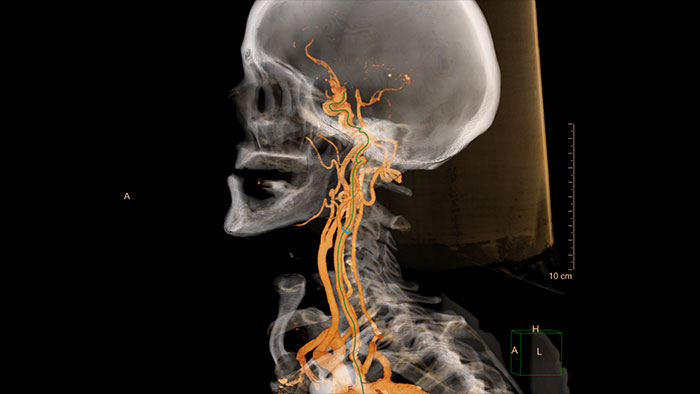

Advanced Vessel Analysis (AVA)

Multi Modality Advanced Vessel Analysis (AVA)

Comprehensive vascular analysis planning

Designed to examine and quantify different types of vascular lesions from CTA and MRA scans. It accommodates different modes of inspection, allows labeling different vascular lesions, and helps navigating through multiple findings.

Demonstrated to reduce the post-processing time by 50% when compared to manual Head & Neck CT angiography (CTA) analysis*.

advanced vessel analysis thumbnail

Benefits

• Ability to choose which Head & Neck Bone Removal method to be used (Standard vs. Smooth).

• Customizable Volume rendering “smoothness” for the 3D Head & Neck vascular structure using a smoothness control.

* Ardley N et al. Efficacy of a new post processing workflow for CTA head and neck. ECR 2013 / C-1760.